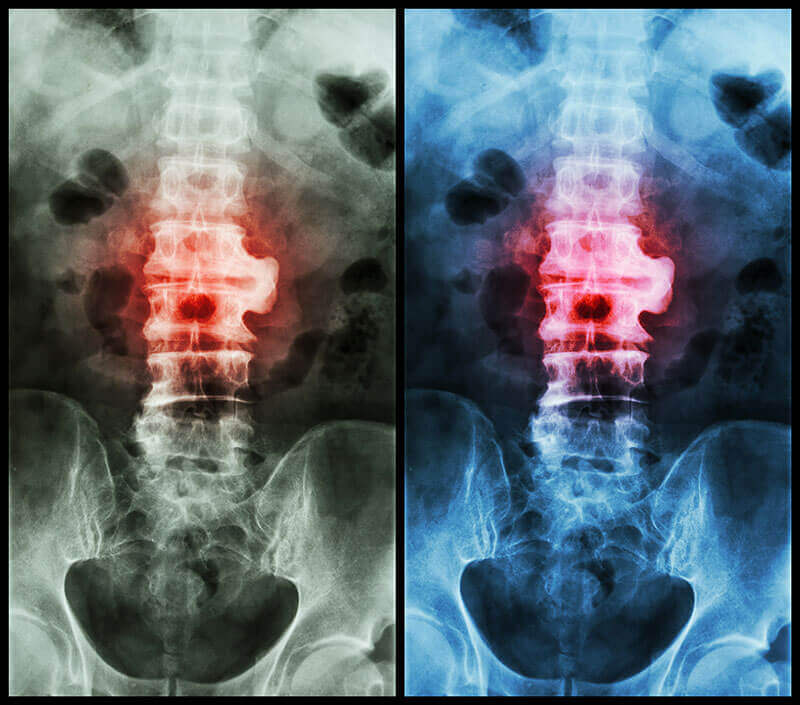

Diagnosticul de spondiloza se face prin scanari specifice, cum ar fi scanarea RMN sau scanarea CT a coloanei vertebrale. Aceste scanari vor arata ingustarea spatiilor articulare dintre corpurile vertebrale, ingrosarea discurilor intervertebrale, precum si evidentierea degenerarii atat a discurilor, cat si a vertebrelor.O simpla radiografie arata proeminente mici cunoscute sub numele de osteofite de la marginea vertebrelor. Prezenta osteofitelor este o indicatie a osteoartritei. Aceste descoperiri sunt destul de tipice si, combinate cu un istoric clinic, pot face posibila diagnosticarea spondilozei.